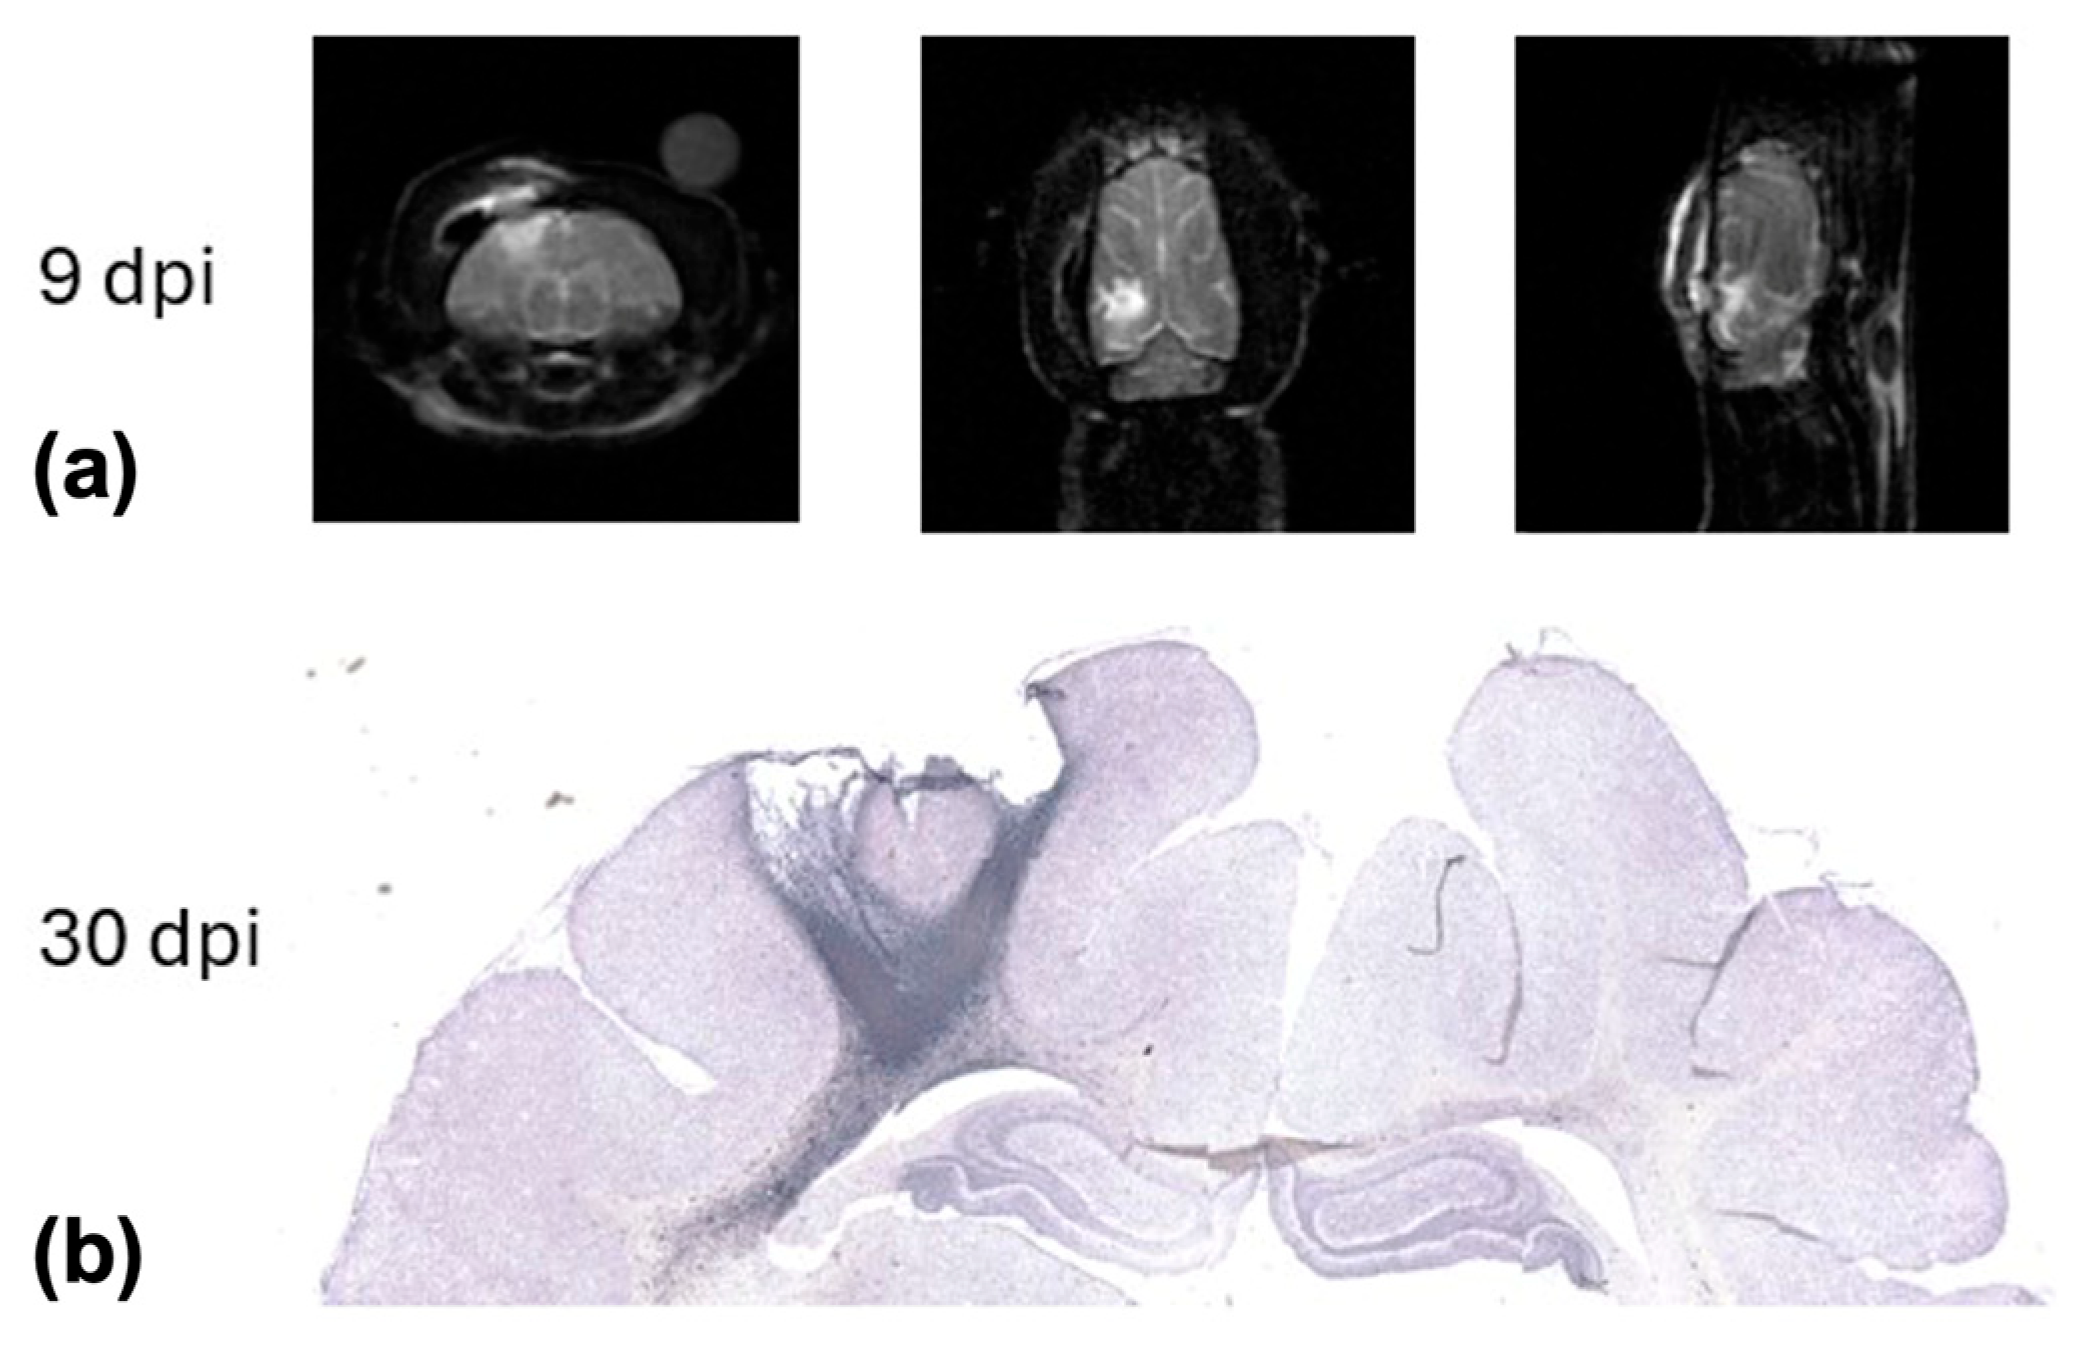

- Hutchinson, E.B.; Schwerin, S.C.; Radomski, K.L.; Irfanoglu, M.O.; Juliano, S.L.; Pierpaoli, C.M. Quantitative MRI and DTI Abnormalities During the Acute Period Following CCI in the Ferret. Shock 2016, 46, 167–176. [Google Scholar] [CrossRef]

- Schwerin, S.C.; Hutchinson, E.B.; Radomski, K.L.; Ngalula, K.P.; Pierpaoli, C.M.; Juliano, S.L. Establishing the Ferret as a Gyrencephalic Animal Model of Traumatic Brain Injury: Optimization of Controlled Cortical Impact Procedures. J. Neurosci. Methods 2017, 285, 82–96. [Google Scholar] [CrossRef]